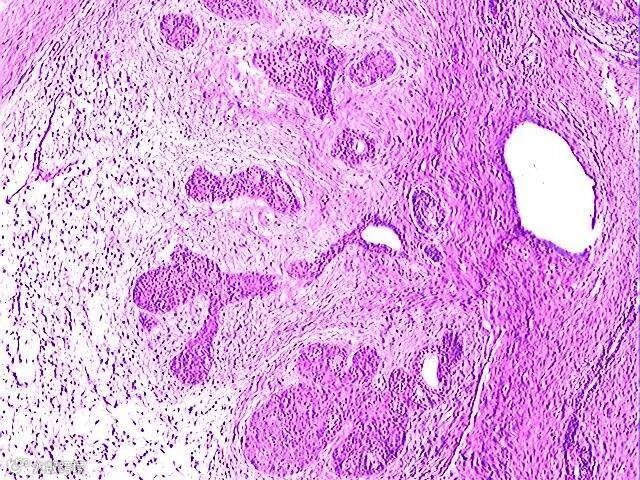

肿瘤

肿瘤被认为是“永不愈合的创伤”,一些临床上广泛应用的抗肿瘤药物,由于半衰期较短,在治疗肿瘤时的应用剂量往往较高,给病人带来严重副作用。

通过间充质干细胞实施肿瘤靶向治疗,在实现更优治疗效果的同时,可大幅降低临床应用药物剂量。

中科院上海生命科学研究院健康科学研究所的时玉舫研究组认为,间充质干细胞作为抗肿瘤药物载体,在肿瘤靶向治疗中有望发挥重要作用。